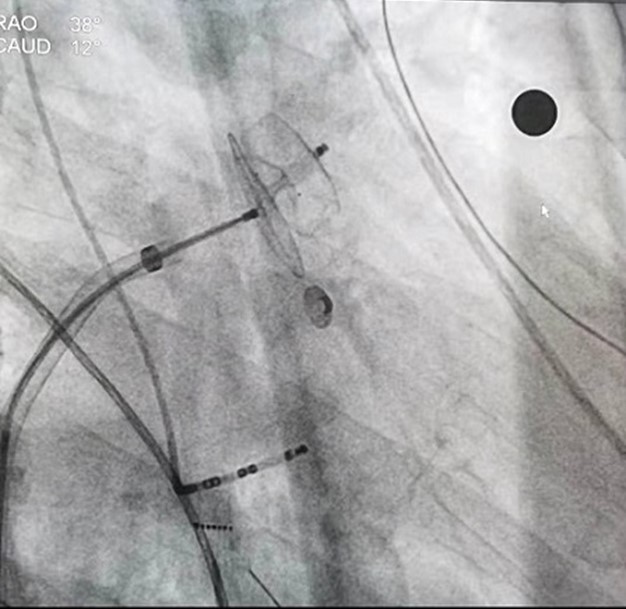

X线下所示左心耳封堵器